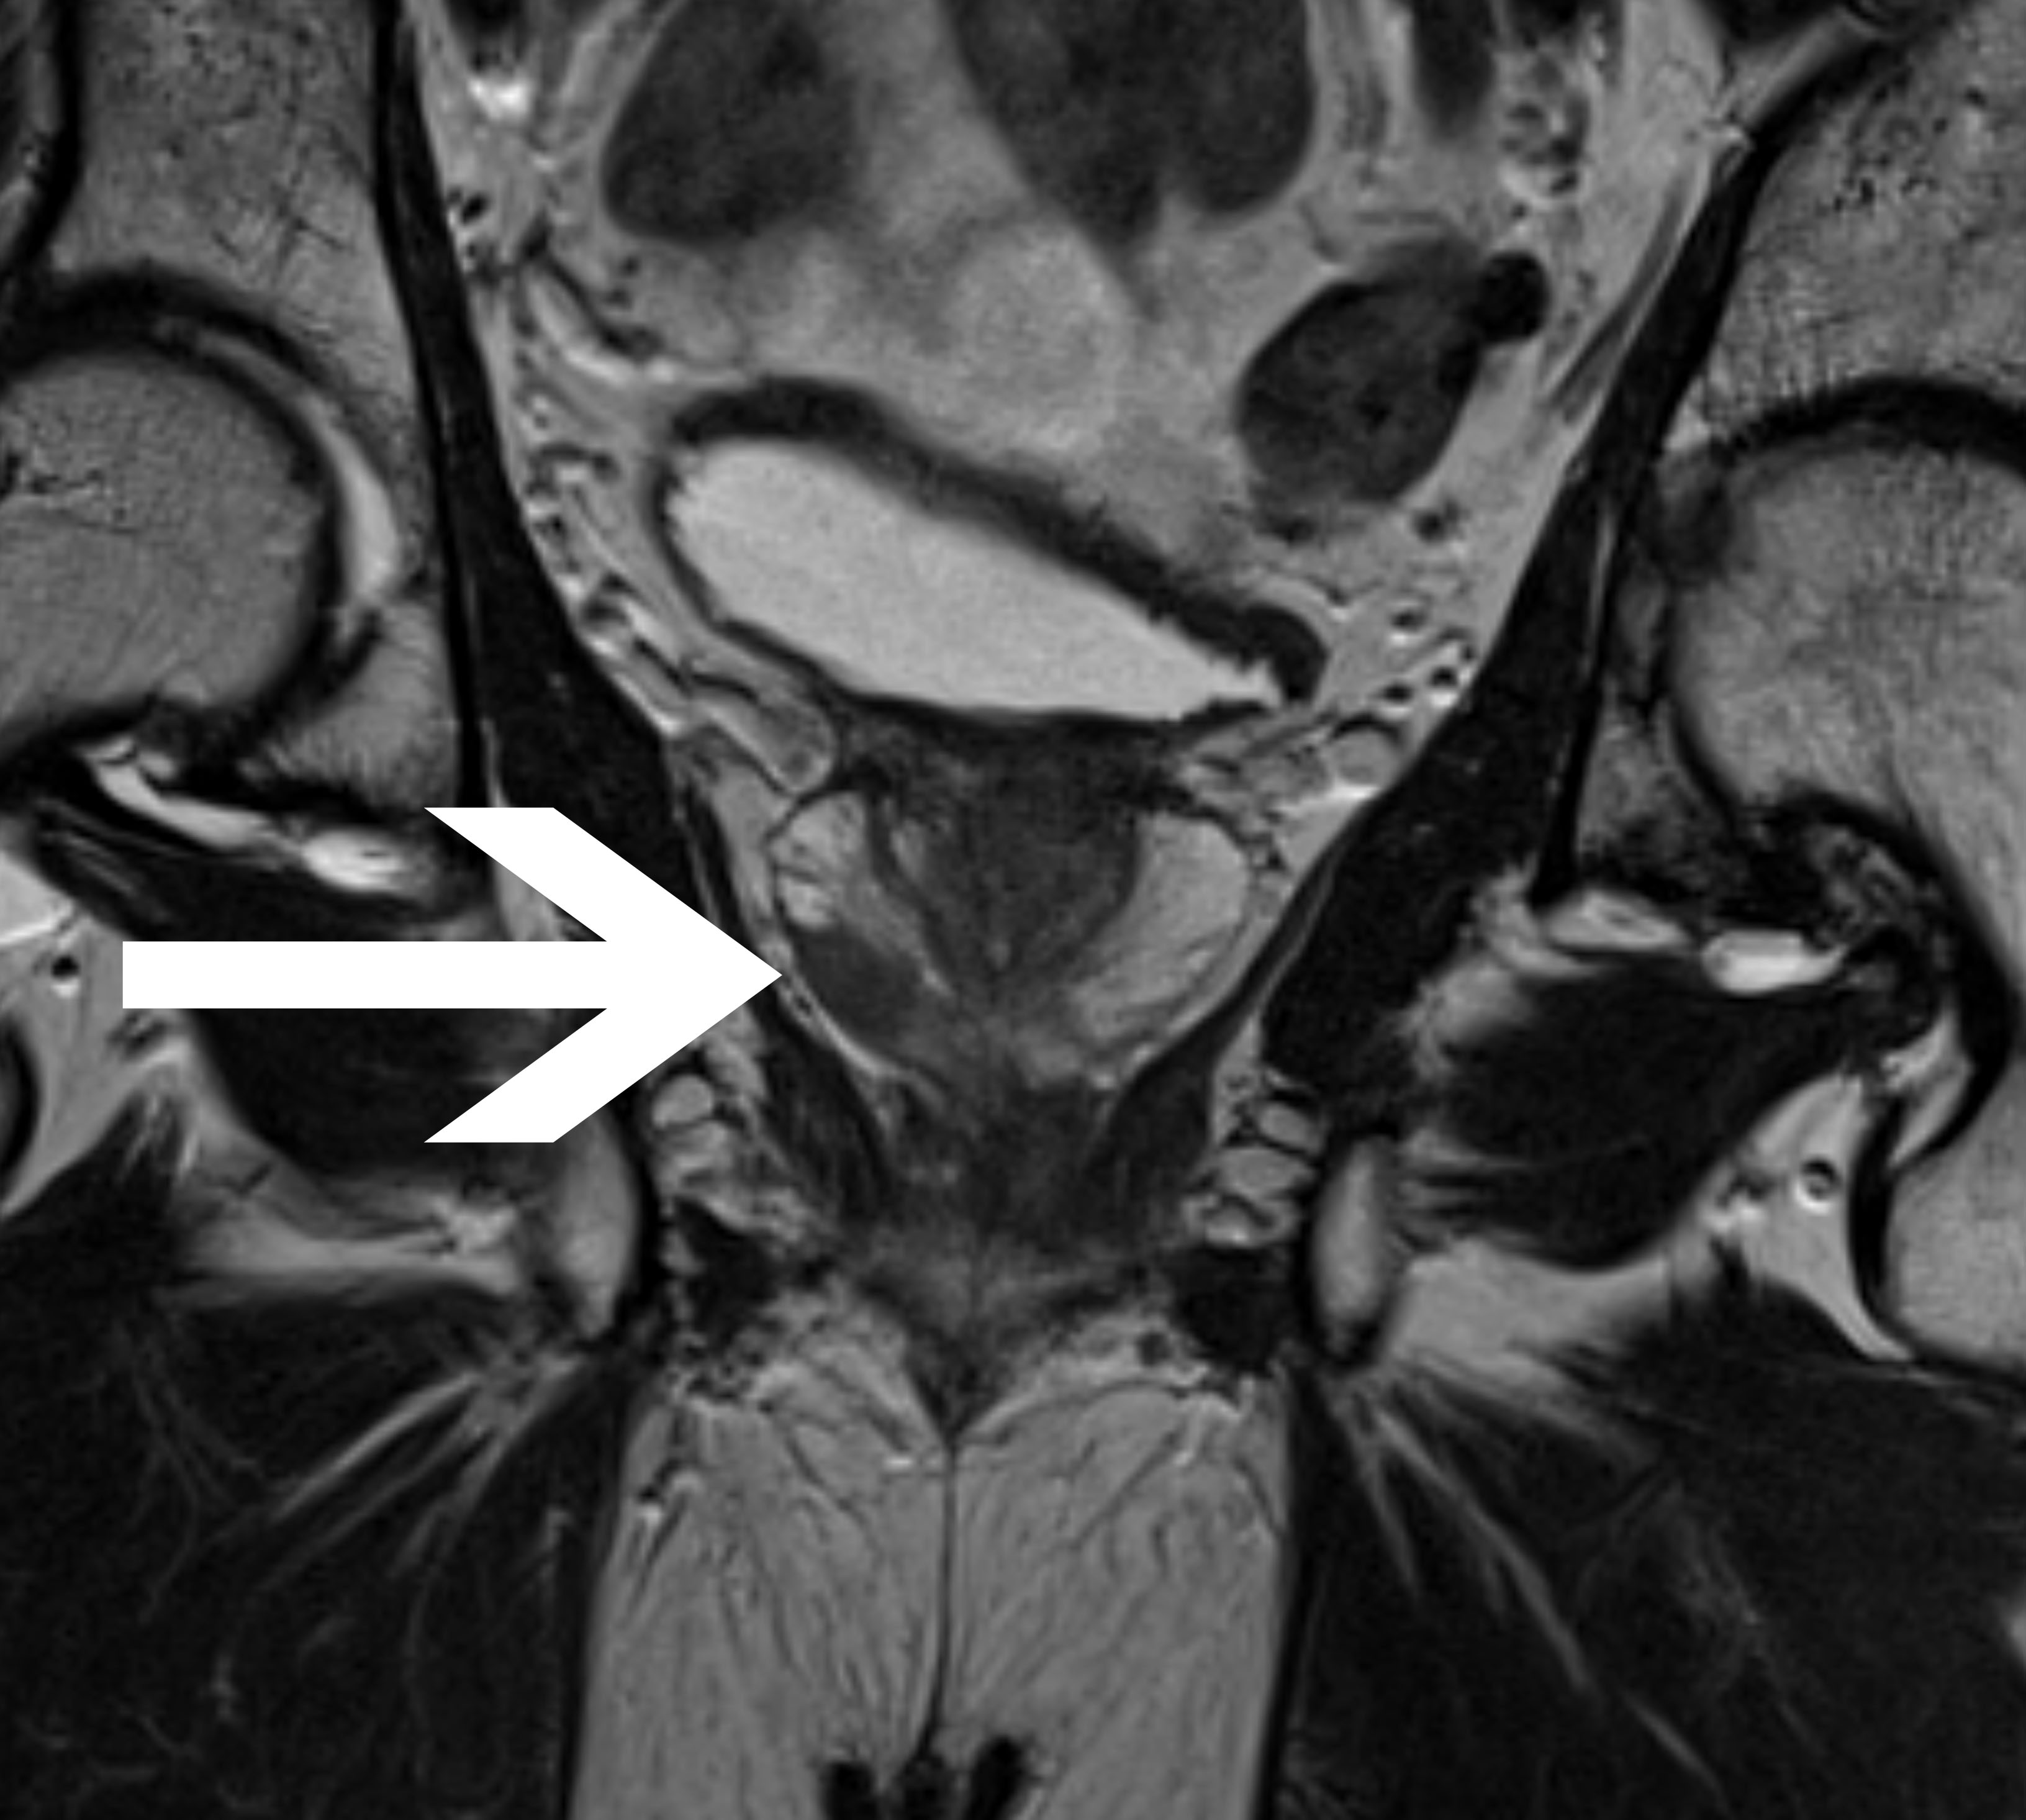

a

Abb1:

Histologisch gesichertes einseitiges

Prostatakarzinom in der

peripheren Zone rechts in:

koronar (Abb.1a) und transversal (Abb.1b)

ausgerichteter T2-TSE-Sequenz.